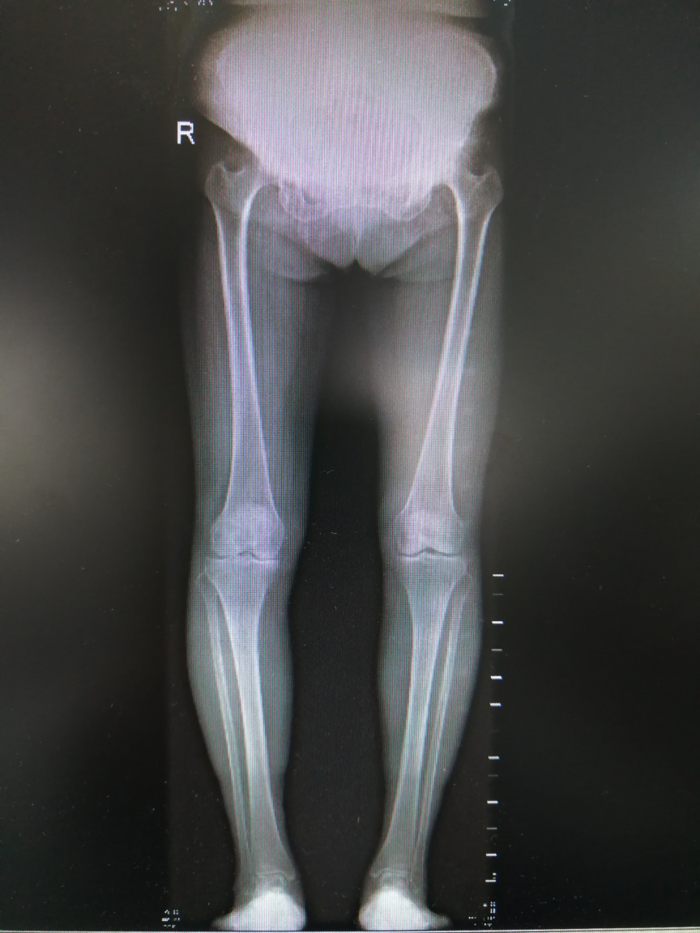

下图为患者2019年01月15日双下肢力线全长X光片

上海交通大学医学院附属第九人民医院骨科王金武教授针对患者目前病情,推荐患者佩戴3D打印个性化膝关节矫形器,并为其讲解病情及治疗效果。希望通过3D打印矫形器缓解膝关节内髁软骨的受力,减少其磨损并延缓其退变,有望解除困扰阿婆数年的膝关节疼痛。